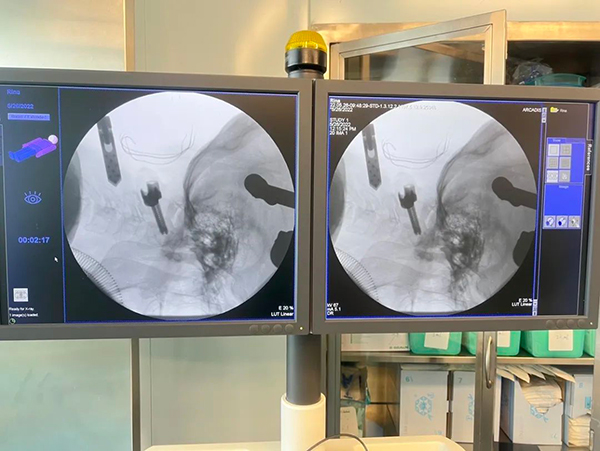

2022年5月26日,北京胸科医院骨科医疗团队联合麻醉科手术室医疗护理团队,首次利用三维导航系统为一名寰枢椎结核的患者顺利实施了颈枕固定融合手术。

寰枢椎手术可以称得上是脊柱手术中的“天花板”,曾被一度认为是脊柱外科的手术禁区。这主要是因为寰枢椎的特殊解剖结构导致的。寰枢椎是头颈部之间的重要枢纽,此处的病灶若不及时进行手术治疗,患者随时面临截瘫,甚至是危及生命的风险。但在寰枢椎这个狭小的区域内存在着脊髓和椎动脉等关乎着患者生命安危的重要组织。对其进行椎弓根螺钉固定,既要保证置入螺钉的精准度又要巧妙地避开这些重要组织结构,再加上结核手术本身的病灶清理的难度,这种手术的操作就如同在刀尖上行走。为保证手术的安全性,术中采用了先进的三维导航系统设备辅助。它可以使医生在显示器中实时观察到椎弓根螺钉置入的路径和与周围重要组织之间的安全距离,从而提高了手术的精确性和安全性。